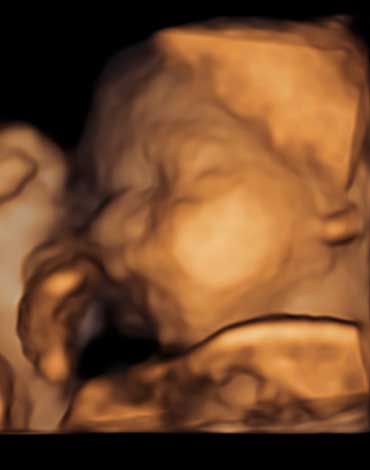

All photos are from our equipment and are of our actual clients.